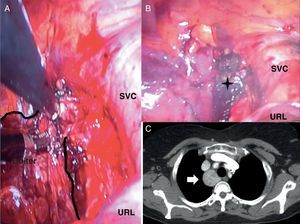

A) Se muestra el bocio parcialmente resecado. La resección se realiza mediante pinzas endoscópicas y LigaSure®. B) La estrella muestra el lecho quirúrgico. C) TC torácica (corte axial): se observa una masa paratraqueal de 3cm (marcada con una flecha blanca) en la región paramediastínica derecha.

SVC: vena cava superior; URL: lóbulo superior derecho.